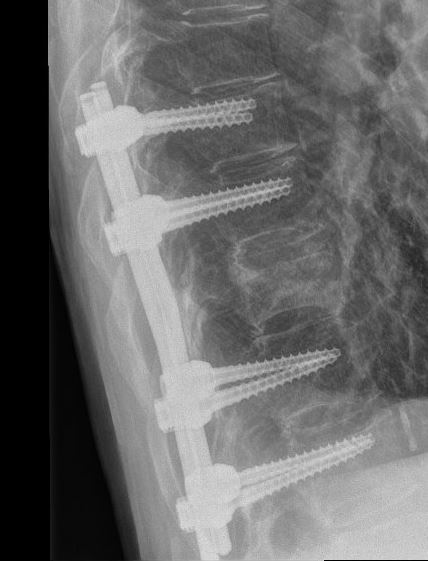

Indien u geopereerd moet worden, zijn er meerdere opties. Meestal zal er gebruik worden gemaakt van schroeven en staven aan de achterzijde van de wervelkolom om de wervels boven en onder de breuk aan elkaar vast te zetten en daarmee de breuk te stabiliseren. Soms is het noodzakelijk om aanvullend nog een stabiliserende operatie aan de voorkant te verrichten.

Zoals elke operatie, heeft ook een operatie aan de rug kans op complicaties, zoals ontstekingen van de wond, beschadiging van het ruggenmerg of zenuwen, of het alsnog inzakken van de breuk na de operatie.

Na de operatie krijgt u soms nog enkele dagen bedrust en zult u samen met de fysiotherapie het mobiliseren hervatten. Uw chirurg bepaalt of u na de operatie nog aanvullend een corset moet gebruiken.